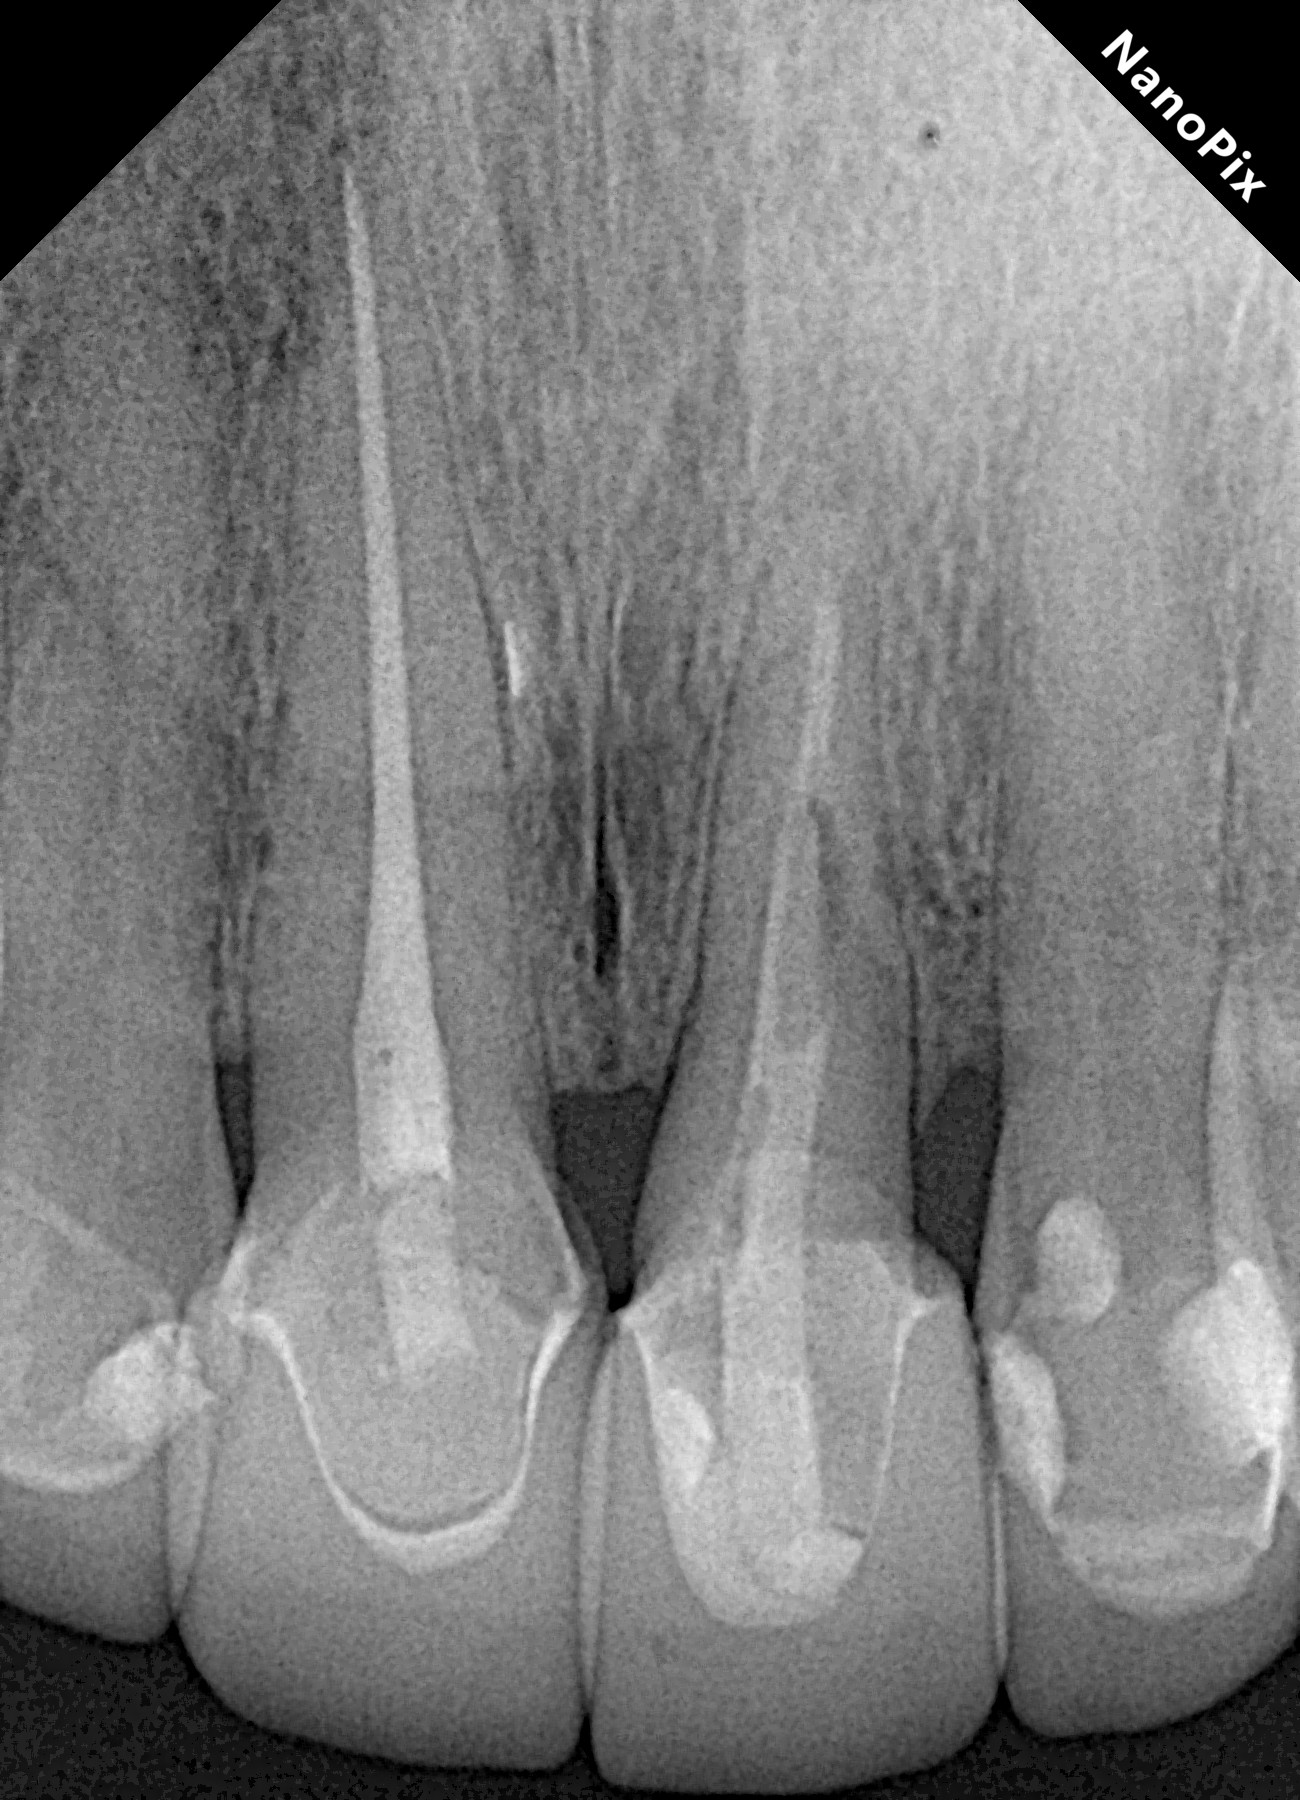

Fig. 2: Post-op radiograph of the tooth extruded by approximately 6 mm and rotated by 180°, locating the deeper zone of the fracture towards the mesial aspect.

After removing the metal–porcelain crown and disinfecting the affected area using a gauze dampened with 2% chlorhexidine (GLUCO-CHeX 2%, CERKAMED), syndesmotomy was performed with a No. 15c scalpel, followed by luxation of the root using a small periotome. Luxation forces were applied only to the first 3 mm of the radicular structure at the mesial aspect with the objective of avoiding damage to the periodontal ligament, which was intended to remain in an infra-osseous position. Once the tooth had been loosened, it was extruded by approximately 6 mm and rotated by 180° (Fig. 2). The rotation was performed with the purpose of positioning healthy periodontal ligament fibres in the distal area because the crestal bone already had an oblique defect at this site. Usually the bone follows the extruded periodontal ligament fibres during this type of procedure, making vertical bone gain possible.8, 15, 16 The rotation also allowed us to limit the extent of extrusion. The extrusion and rotation were managed with forceps, grasping only the coronal portion of the tooth, which was planned to remain in a supra-osseous position after the treatment.